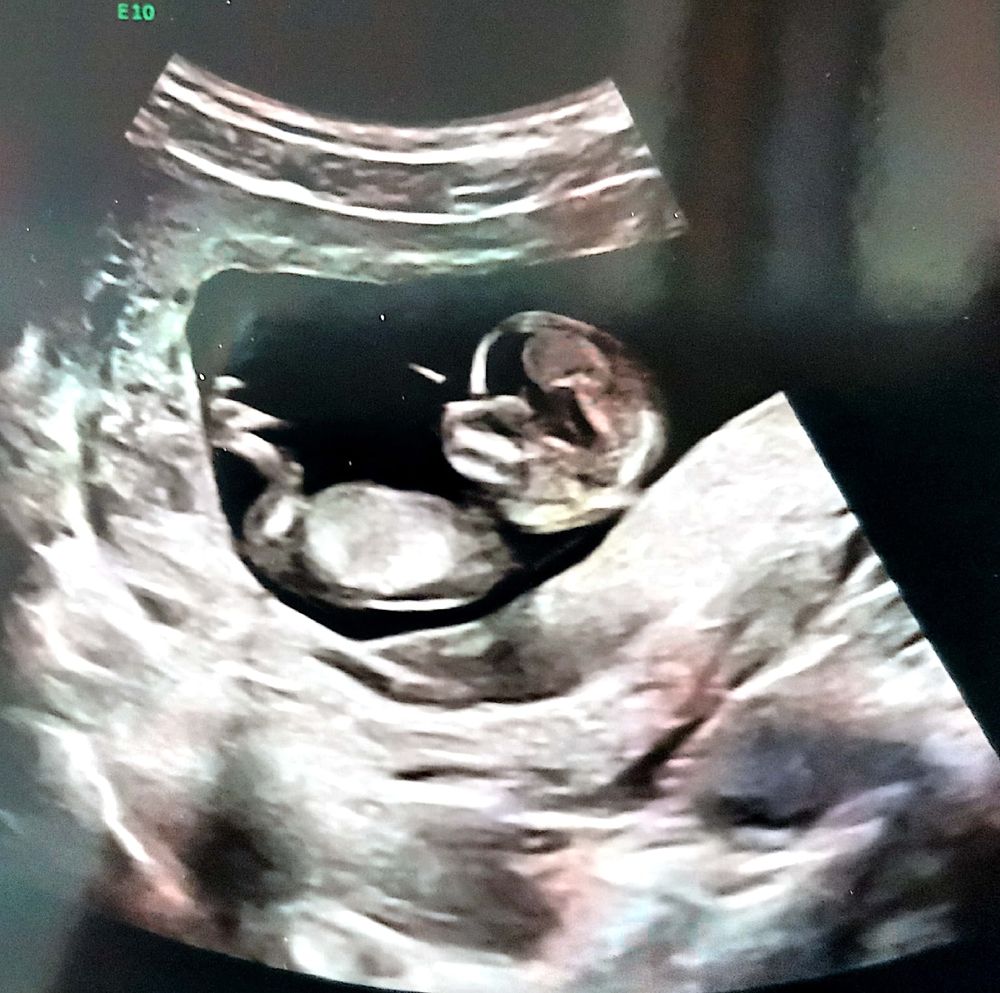

Направила меня врач на скрининг-1 в ПЦ на УЗИ и биохимию и вот:

Между тем, как я делала бесплатный скрининг в ПЦ и моим походом к врачу для её пояснений я сделала ещё платный скрининг, но уже в Белгороде.

Где нам, собственно, предположили девочку💞. Но тут нашли полное предлежание плаценты. Тадададаааам....🙀

А вот и УЗИ😌:

Всмысле нарушение кровотока правой маточной артерии... Что ни УЗИ, то новые приколы. Зато ПОЛНОЕ предлежание испарилось, это как🤔? Плацента могла подняться за 3 недели? Если да, то я счастливый как никто 😄😌